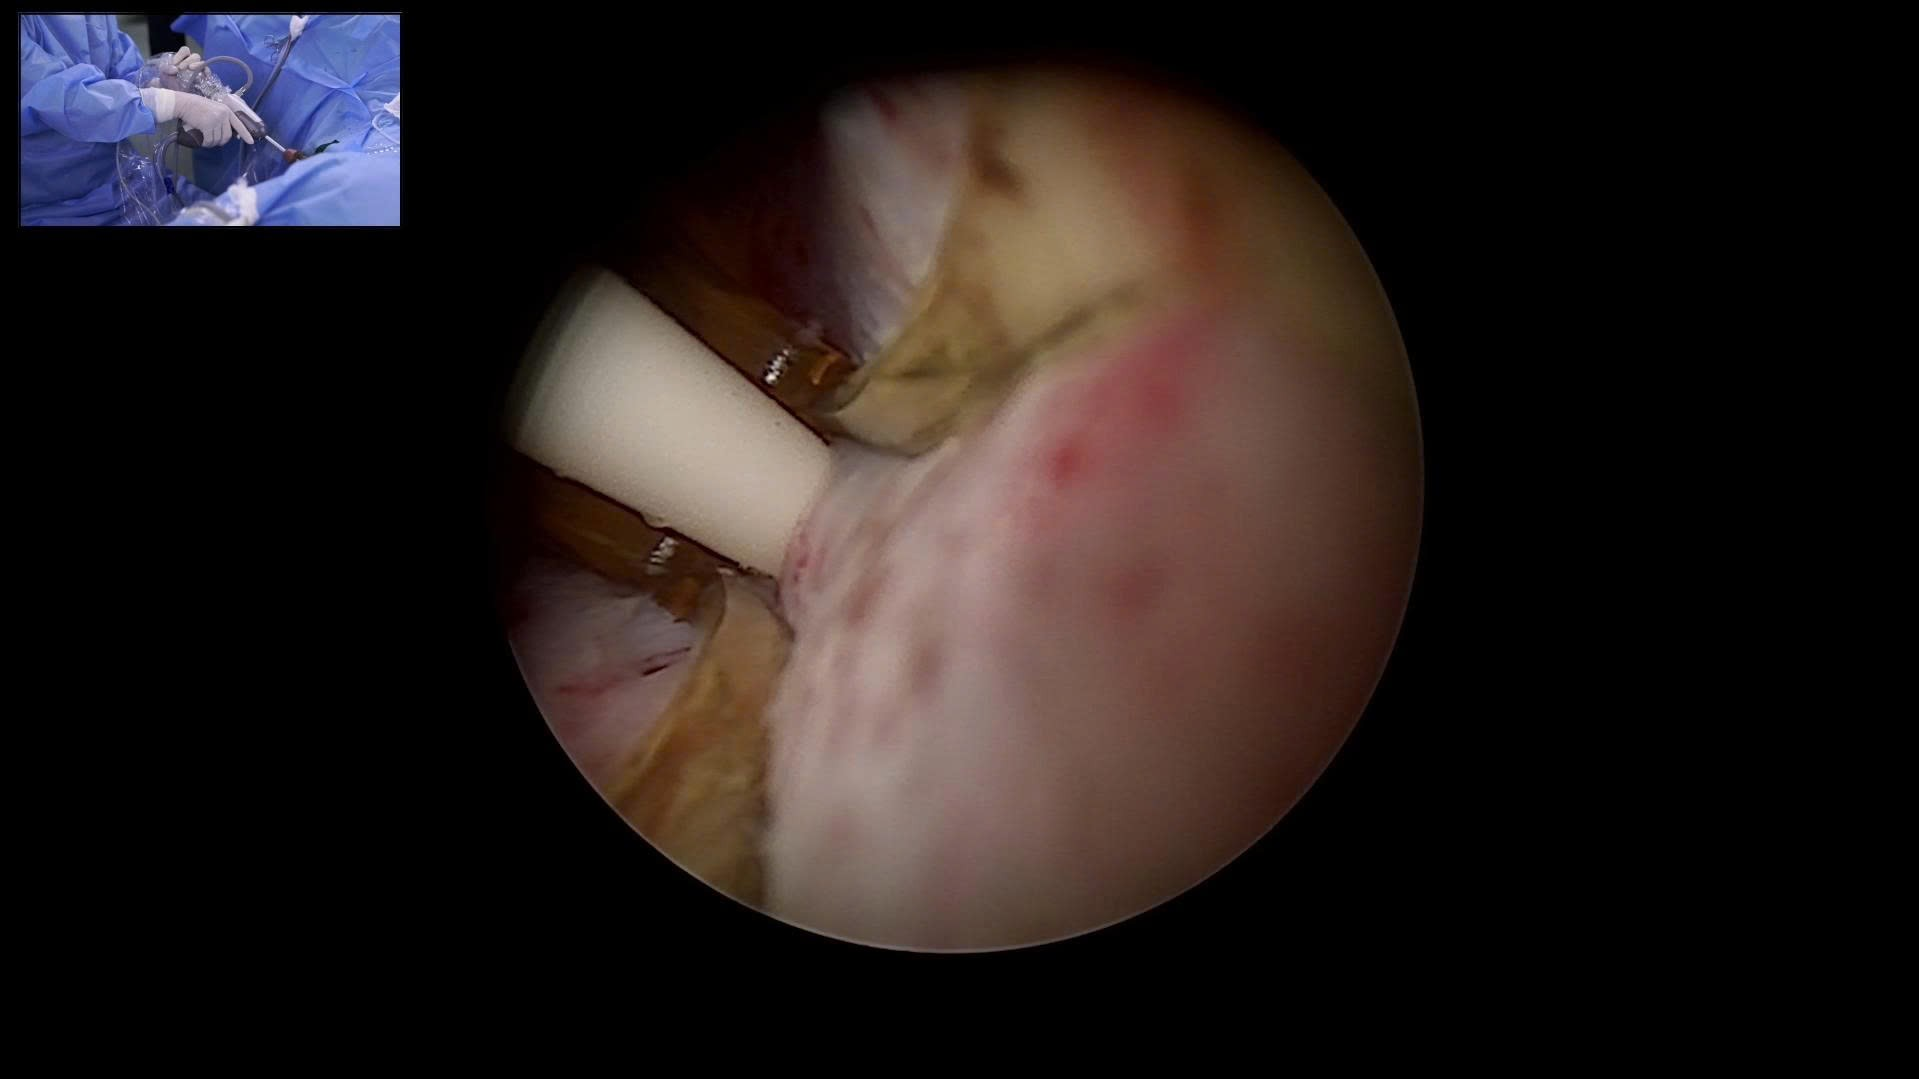

Điều trị bướu cổ phụ thuộc vào nguyên nhân, kích thước bướu và mức độ ảnh hưởng đến chức năng tuyến giáp. Với bướu nhỏ, không triệu chứng và chức năng tuyến giáp bình thường, người bệnh thường chỉ cần theo dõi định kỳ bằng siêu âm và xét nghiệm hormon. Nếu do thiếu i-ốt, bác sĩ sẽ khuyến nghị bổ sung qua muối i-ốt hoặc chế độ ăn. Trường hợp cường giáp, điều trị bằng thuốc kháng giáp, i-ốt phóng xạ hoặc phẫu thuật để giảm mô tuyến giáp. Nếu suy giáp, cần dùng hormon tuyến giáp tổng hợp (levothyroxine) để thay thế. Với bướu to gây chèn ép, nghi ngờ ung thư hoặc nhân giáp phát triển nhanh, phẫu thuật cắt tuyến giáp là phương pháp tối ưu. Ngoài ra, một số bệnh viện hiện áp dụng đốt sóng cao tần (RFA) cho nhân giáp lành giúp thu nhỏ bướu mà không cần phẫu thuật.